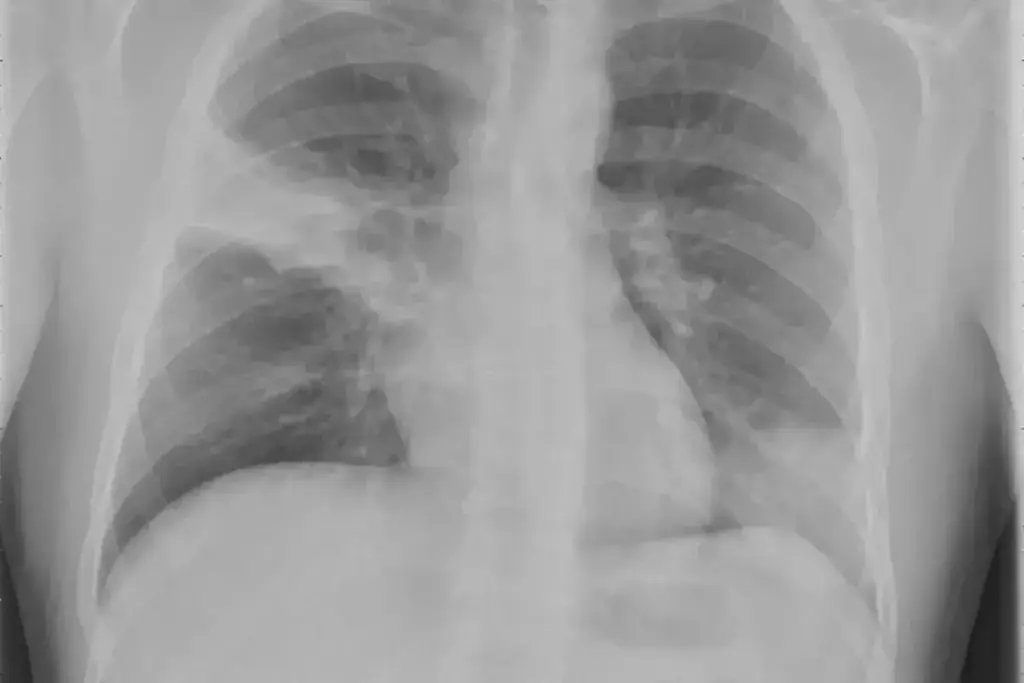

Understanding Bacterial Pneumonia Pathophysiology

image 3360 LIV Hospital

Bacterial pneumonia is a complex disease. It happens when a pathogen and the host’s immune system interact. Streptococcus pneumoniae and Haemophilus influenzae are the main culprits, causing severe lung infections.

Common Bacterial Pathogens and Infection Mechanisms

Bacterial pneumonia often starts in the upper respiratory tract. Streptococcus pneumoniae is the top cause, found in many cases around the world. It spreads through droplets and causes inflammation and infection in the lungs.

The bacteria stick to and invade lung tissue, starting an inflammatory response. This leads to symptoms like cough, fever, and trouble breathing. For more info, check out studies on reputable medical databases.

Pleural effusion is when fluid builds up in the pleural space. If this fluid gets infected, it can turn into empyema. We use chest X-rays and CT scans to diagnose these conditions.

Lung abscess formation is a complication of bacterial pneumonia. It’s when a cavity filled with pus forms in the lung. We use chest X-rays and CT scans to diagnose lung abscesses.

Doctors use a few methods to diagnose. They look at the patient, do a chest X-ray, and run lab tests. These include blood cultures and sputum analysis.